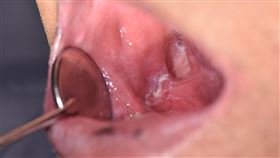

陳昇口腔長瘤 醫師揭口腔癌3大症狀

國泰綜合醫院口腔顎面外科李嘉鐸醫師表示,提到口腔腫瘤...